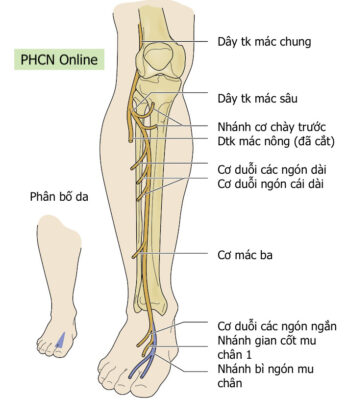

Dây thần kinh mác chung là một dây thần kinh lớn chi phối cho chi dưới. Nó là một trong hai nhánh chính của dây thần kinh tọa (nhánh kia là thần kinh chày) và nhận các sợi từ các ngành sau của các rễ thần kinh từ L4 đến S2. Dây thần kinh mác chung tách dây thần kinh chày ở phía dưới mặt sau đùi gần hố khoeo. Sau khi tách khỏi dây thần kinh chày, nó tiếp tục chạy xuống đùi, chạy phía sau dưới đến cơ nhị đầu đùi (phân nhánh vận động cho đầu ngắn của cơ nhị đầu đùi), và bắt chéo ra ngoài đến đầu cơ bụng chân ngoài qua vách gian cơ sau. Sau đó, dây thần kinh này tiếp tục đi ngang ra ngoài, vòng quanh cổ xương mác. Trước khi đến đầu xương mác, nó phân nhánh cảm giác (bì cẳng chân ngoài) để phân bố cảm giác cho da mặt trên ngoài cẳng chân. Gần đầu xương mác, dây thần kinh mác chung chia thành hai nhánh tận, dây thần kinh mác nông (superficial peroneal nerve, SPN) và dây thần kinh mác sâu (deep peroneal nerve , DPN).

Dây thần kinh mác nông chi phối khoang ngoài của cẳng chân, còn dây thần kinh mác sâu chi phối khoang trước của cẳng chân và mu bàn chân.

- Dây thần kinh mác nông chủ yếu là dây thần kinh cảm giác, phân bố cho:

- Về vận động: Khoang ngoài

- Cơ mác dài

- Cơ mác ngắn

- Về cảm giác:

- Trước ngoài cẳng chân, hầu hết mu bàn chân

- Về vận động: Khoang ngoài

- Dây thần kinh mác sâu chủ yếu là vận động, phân bố cho:

- Về vận động: Khoang trước

- Cơ chày trước

- Cơ duỗi ngón cái dài

- Cơ duỗi các ngón dài

- Cơ mác ba

- Về cảm giác

- Khoảng kẽ ngón thứ nhất mu chân.

- Về vận động: Khoang trước

Hình 1: Phân bố cảm giác và vận động của dây thần kinh mác chung (màu tím) và mác nông (xanh).

Hình 2. Phân bố cảm giác và vận động của Dây thần kinh mác sâu

Khám cảm giác:

- Giảm cảm giác ở mặt trên ngoài cẳng chân (Hình 1) gợi ý một tổn thương ở cao hơn đầu xương mác (nghĩa là dây thần kinh mác chung). Đánh giá cơ vặn trong bàn chân, để loại trừ tổn thương đồng thời của dây thần kinh chày (nghĩa là tổn thương ở dây thần kinh tọa), tốt nhất với bàn chân gập mu nhẹ.

- Giảm hoặc rối loạn cảm giác ở phần dưới ngoài cẳng chân và hầu hết mu bàn chân gợi ý ảnh hưởng đến dây thần kinh mác nông hoặc phần này của dây thần kinh tọa (Hình 1).

- Trường hợp ảnh hưởng đến dây thần kinh mác sâu, có giảm cảm giác hoặc dị cảm dọc theo khoảng kẽ thứ nhất của bàn chân (Hình 2).